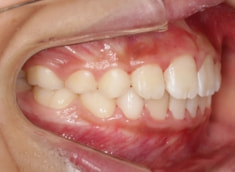

治療中